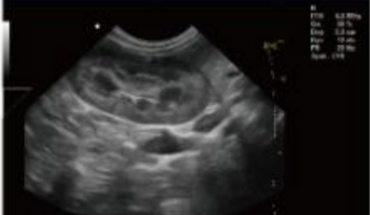

- Equipped with a Wide Range of Probes for Abdominal, Obstetric, Vascular, Cardiac, Small Organ, Urinary Applications

Rich Clinical Application Function